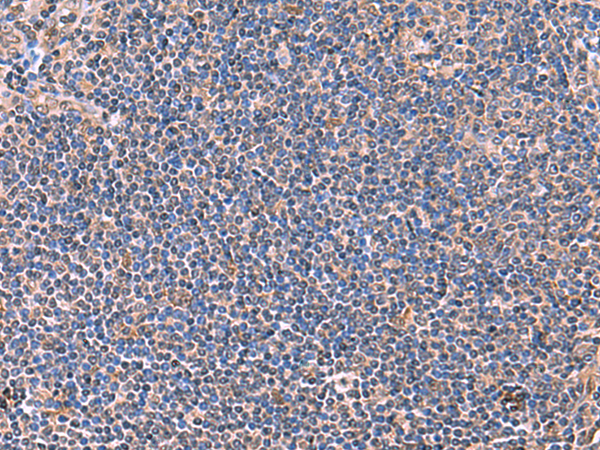

分类: 科研抗体货号: P10191别名: ANF1A2; HELIOS; ZNF1A2; ZNFN1A2应用: WB,IHC反应种属: Human, Mouse